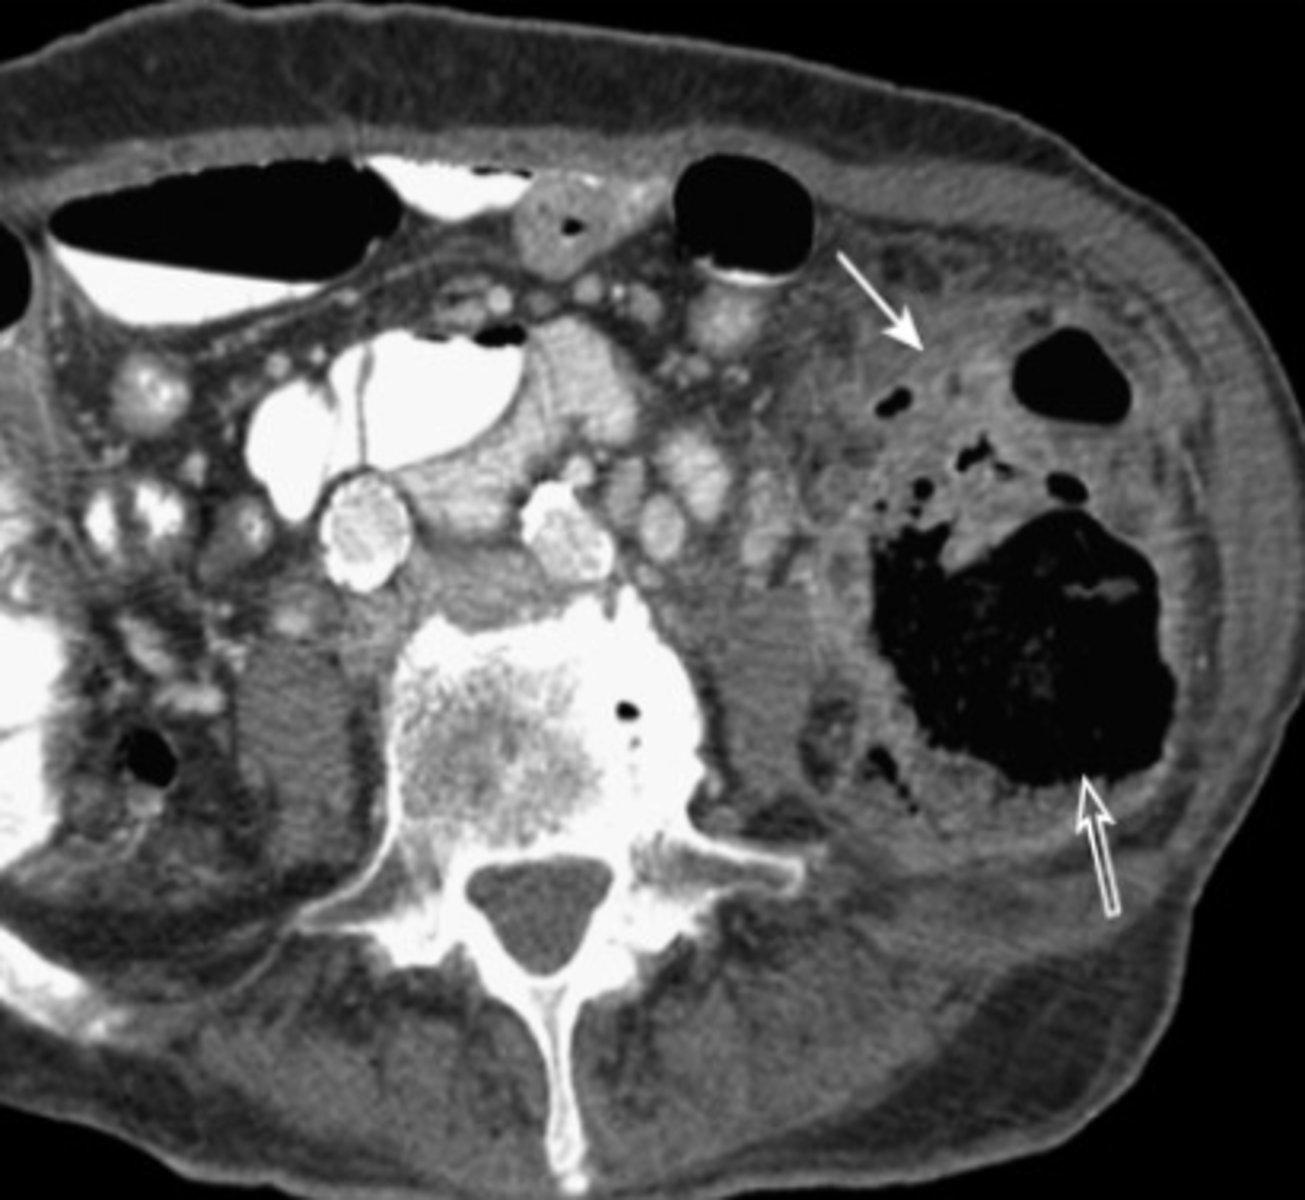

spleen

most highly vascular organ, most injured organ in blunt trauma

CT is diagnostic study of choice

Tx: mostly non-surgical

splenic laceration

hemorrhage and hematoma present, dark fluid is blood surrounding spleen